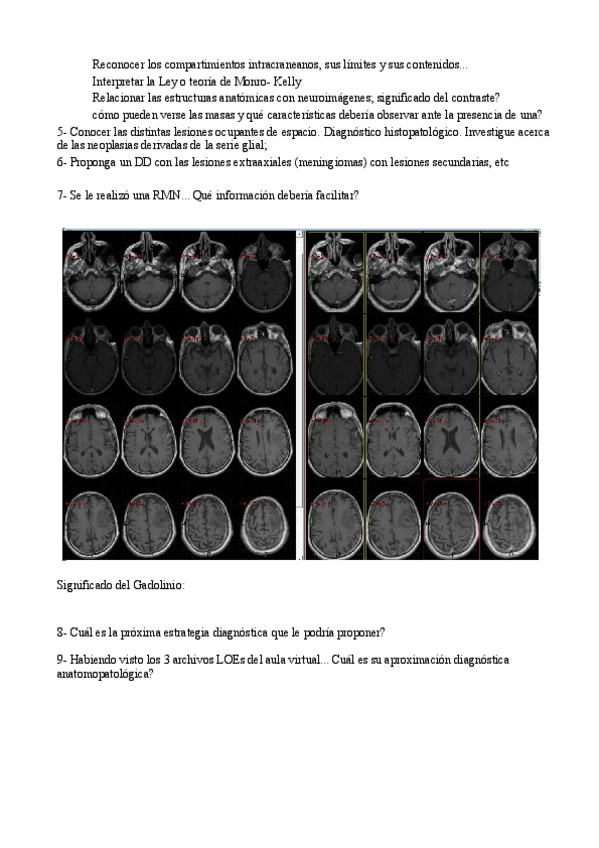

He publicado nuevos apuntes de 4º Neurología: 2021-LOE-Problema-Ciclo-II-LOE.pdf